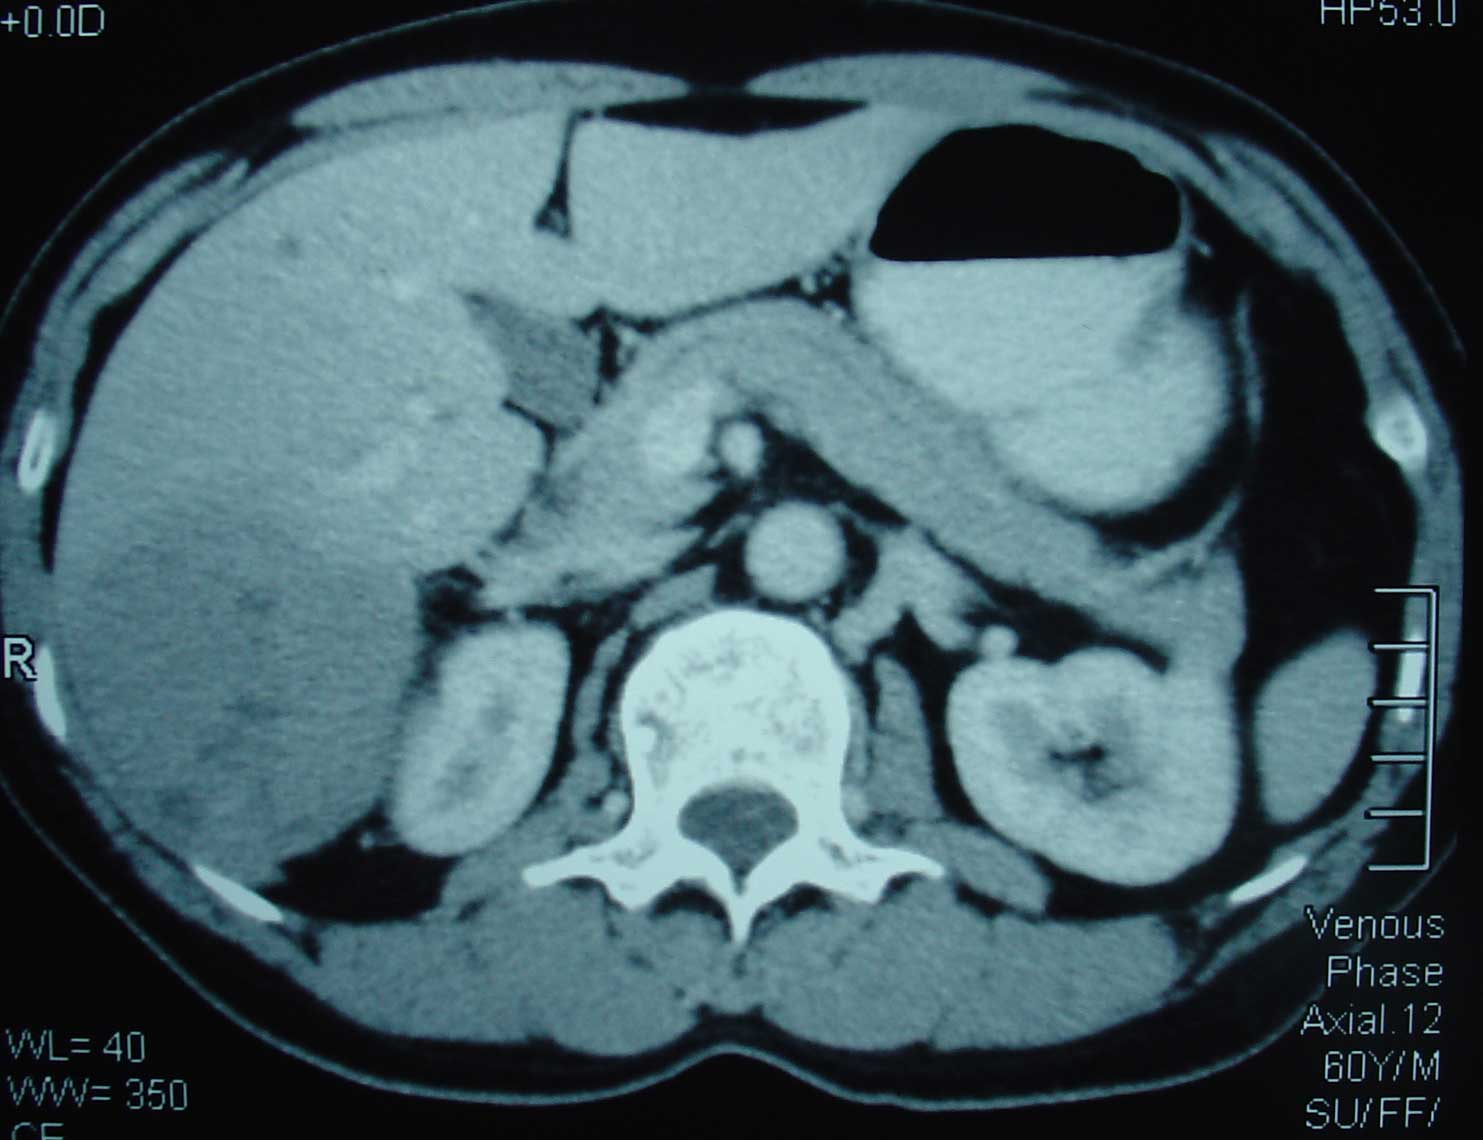

Seam (B984), seoarang wanita berusia 49 tahun, didiagnosa hepatoseluler karsinoma pada Agustus 2003. Hasil CT-abdomen pada 26 Agustus 2003 mengindikasikan:

1.   Massa pada segmen 6 dan 7 liver sebesar 8,7 x 6,6 x 10 cm.

2.   Ruptur pada lobus caudatus.

3.   Nodul-nodul peritoneal.

4.   Trombosis vena porta.

5.   Splenomegali (pembesaran limpa).

6.   Dan kemungkinan metastase ke limpa.